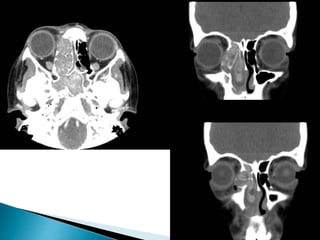

 Most patients with IFS do not have bone

erosion or extension of the disease outside of

the sinuses early in their course when salvage

is most likely. Recent data suggest

that unilateral thickening of nasal mucosa is

the most common initial finding on CT and

rhinoscopy in early disease .

 Unlike chronic invasive fungal sinusitis, acute

infection generally does not demonstrate hyperdense

material within the sinus on non-contrast CT. CT is

particularly effective at assessing bony changes.

Findings include 2:

◦ mucosal thickening: hypoattenuating

◦ opacification of the sinus: soft tissue attenuation

◦ bone destruction: may be extensive or very subtle or even

inapparent (extension through intact bone via vascular

invasion)

◦ fat stranding outside the sinus perimeter

 intraorbital fat

 masticator space

 pterygopalatine fossa

◦ Features of potential complications should also be sought.